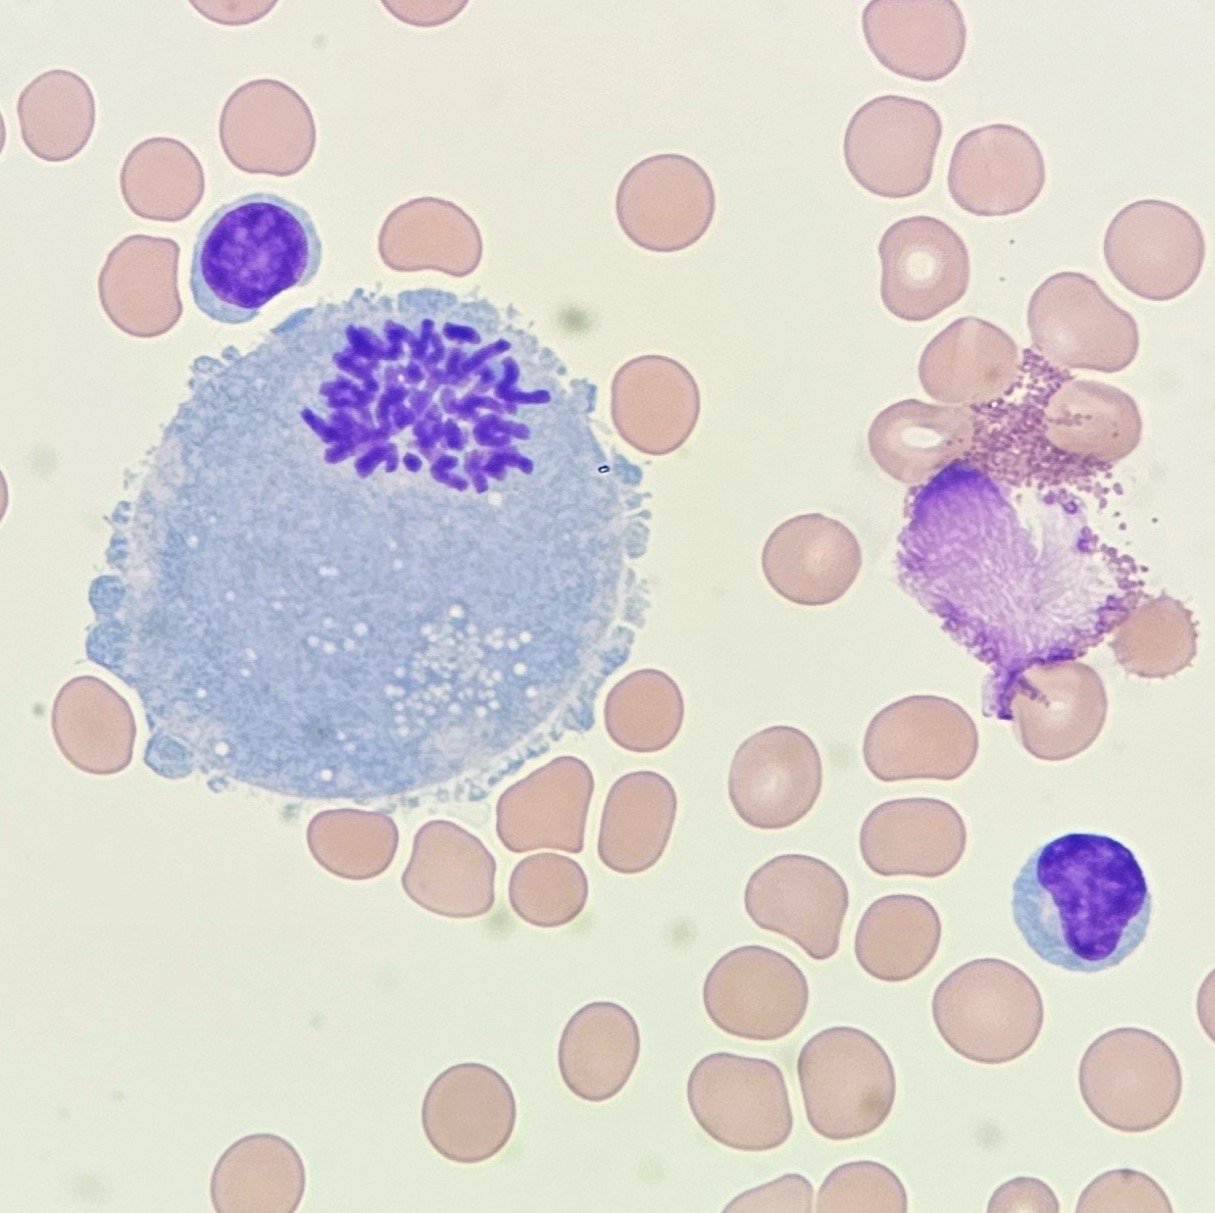

Mesothelial cells are described as having a “fried egg” appearance. They have a round to oval nucleus with smooth borders and evenly distributed chromatin. Nucleloli are usually present. Mesothelial cells may also be multinucleated.

Cells may be seen in clumps, but “windows” between cells still allows for individual counting.

Macrophages are about the same size as mesothelial cells, so the two can often be confused. Macrophages can usually be differentiated by the presence of vacuoles and a lacey chromatin. If both cell types are present and differentiation is difficult, take a look around the slide to get an idea of each kind of morphology before starting a differential.

Both malignant cells and mesothelial cells can clump together. However, malignant cells will not have the windows between cells.